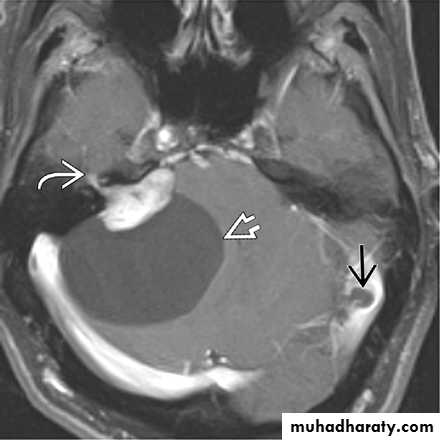

Cerebellopontine angle arachnoid cyst

Developmental Abnormalities of the Nervous System